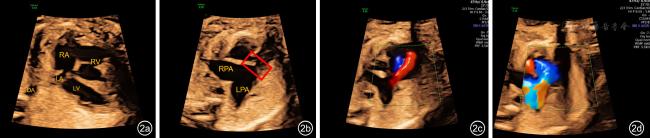

APVS组20例(图2),孕妇平均年龄(27.5±3.6)岁,平均诊断GA(24.9±2.1)周。对照组261例,孕妇平均年龄(30.6±3.6)岁,行胎儿超声心动图检查的GA范围16~37+1周,平均GA(26.9±4.4)周。

图2 肺动脉瓣缺如综合征胎儿四腔心切面及右心室流出道-肺动脉分支切面超声图像。图a为四腔心切面显示左右心比例不对称,右心明显增大,心轴左偏;图b红框标记为肺动脉瓣环处,未见明显瓣叶结构回声。肺动脉主干及左右分支显著扩张,呈“鲸鱼尾”征;图c,d为彩色多普勒图像,显示肺动脉瓣环处往返于右心室与肺动脉之间的高速“穿梭”样血流信号,其中图c为舒张期,可见由明显扩张的肺动脉主干及分支反流进入右心室的红色血流信号;图d为舒张期,可见右心血流经过肺动脉瓣环冲击肺动脉及其分支的蓝色血流信号

注:LA为左心房;LV为左心室;RA为右心房;RV为右心室;LPA为左肺动脉;RPA为右肺动脉;DA为降主动脉